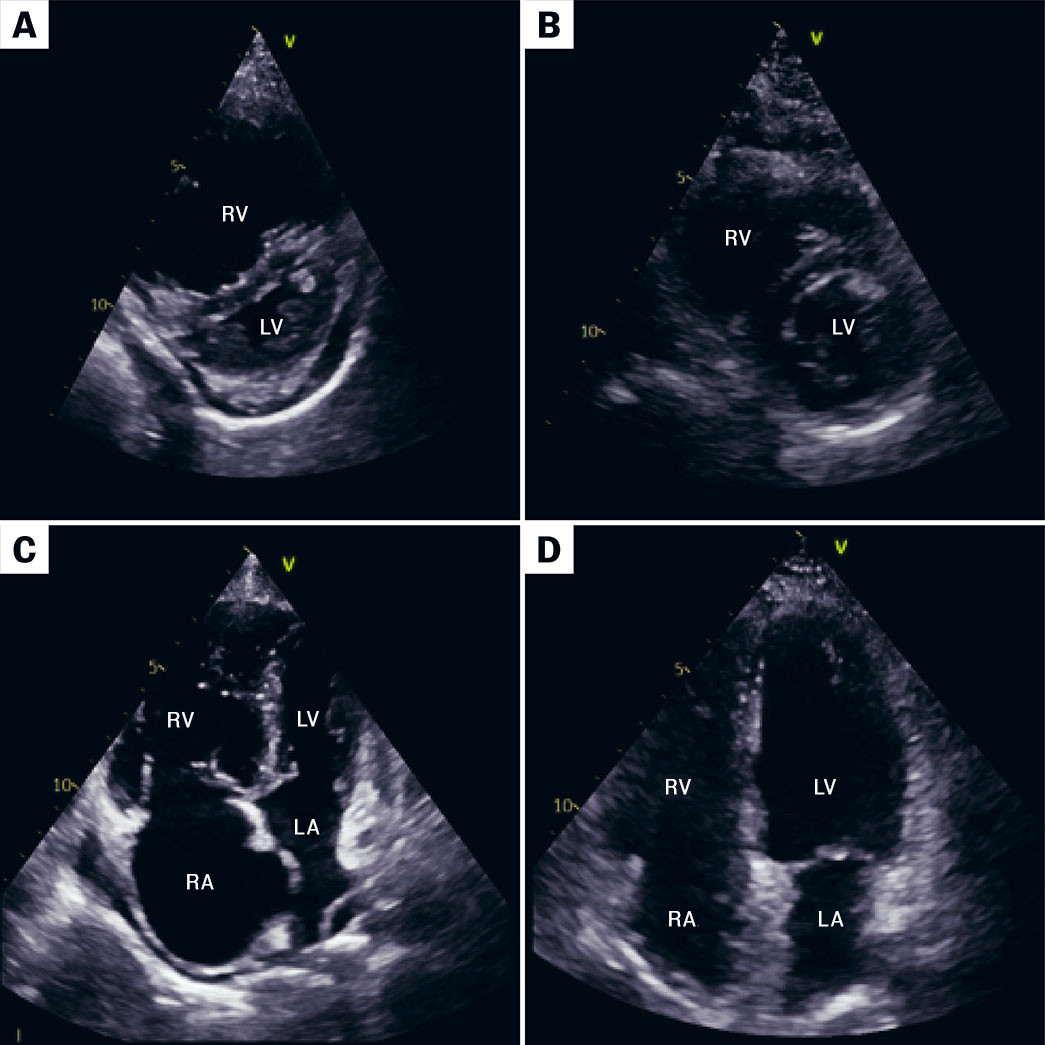

The first step in the workup when CTEPH is suspected is usually echocardiography. Doppler measurement of tricuspid regurgitation velocity can be used to estimate pulmonary artery pressure. In pulmonary hypertension, echocardiography demonstrates left displacement of the interventricular septum, reduced left ventricular filling and reduced stroke volume (Figure 1). Persistent dyspnoea three months or more after pulmonary embolism should be investigated with echocardiography, followed by further workup if there are signs of pulmonary hypertension.